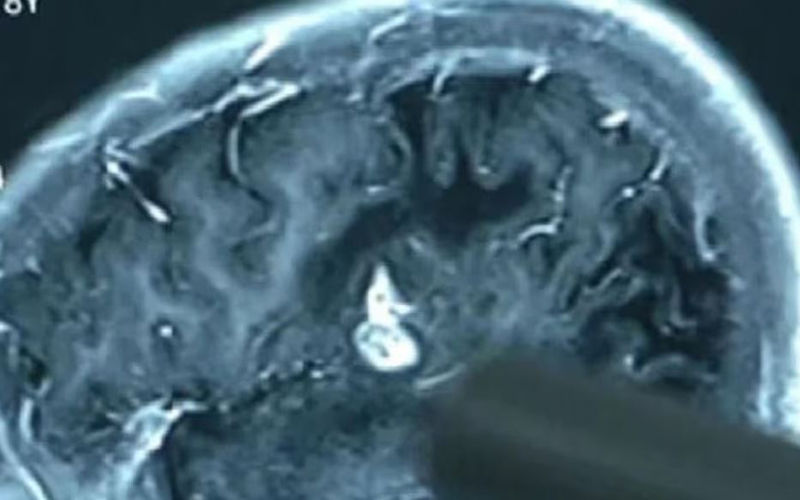

अमेरिका की राजधानी वाशिंगटन से आई मीडिा रिपोर्ट के अनुसार अमेरिका में एक शख्स को लगातार माइग्रेन की शिकायत की थी। इसके बाद जांच में पता चला कि उसके दिमाग में कृमि (टेपवर्म का लार्वा) है। जानकारी के मुताबिक, 52 वर्षीय शख्स बार-बार माइग्रेन की शिकायत कर रहा था। लेकिन कुछ दिनों में ही हालात बिगडऩे लगी और दवाईयों ने काम करना बंद कर दिया।

सीटी स्कैन में पता चला कि लगभग चार महीने से उसके दिमाग में जीवित था और अंडे दे रहा था। यह ऐसा परजीवी कीड़ा है, जो इंसानों और ज जानवरों को संक्रमित करता है। आमतौर पर यह अ आंतों में पाया जाता है, लेकिन कुछ परिस्थितियों में इसके लिए दिमाग तक पहुंचना भी कोई मुश्किल काम नहीं है।